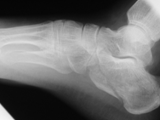

Charcot-foot

Charcot-foot